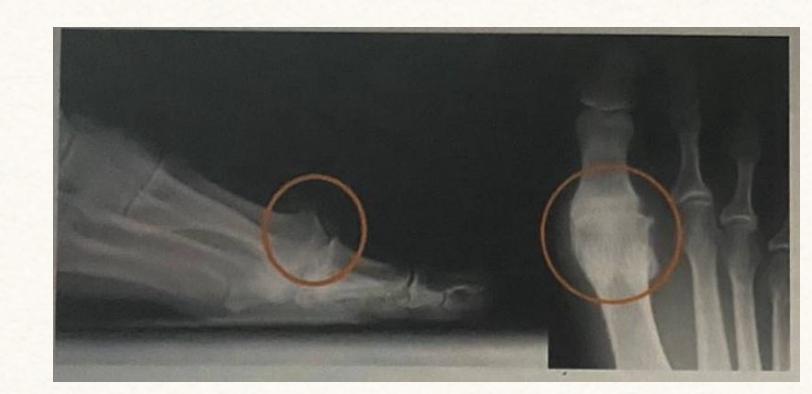

Q8/ What is the type of fracture shown in these pictures?

- A- Salter harris fracture II